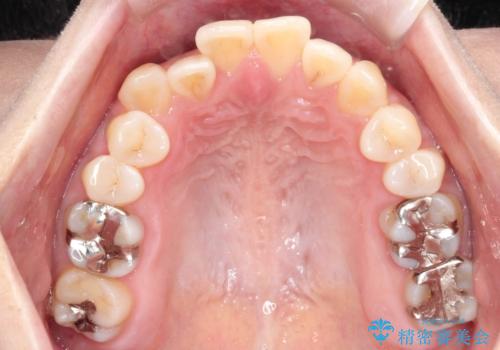

【開咬】笑った時の見た目を改善したい。

- 重度の開咬でしたがインビザラインで適切に治療計画を立て、きれいに仕上がりました。

インビザラインは開咬の治療に向いています。